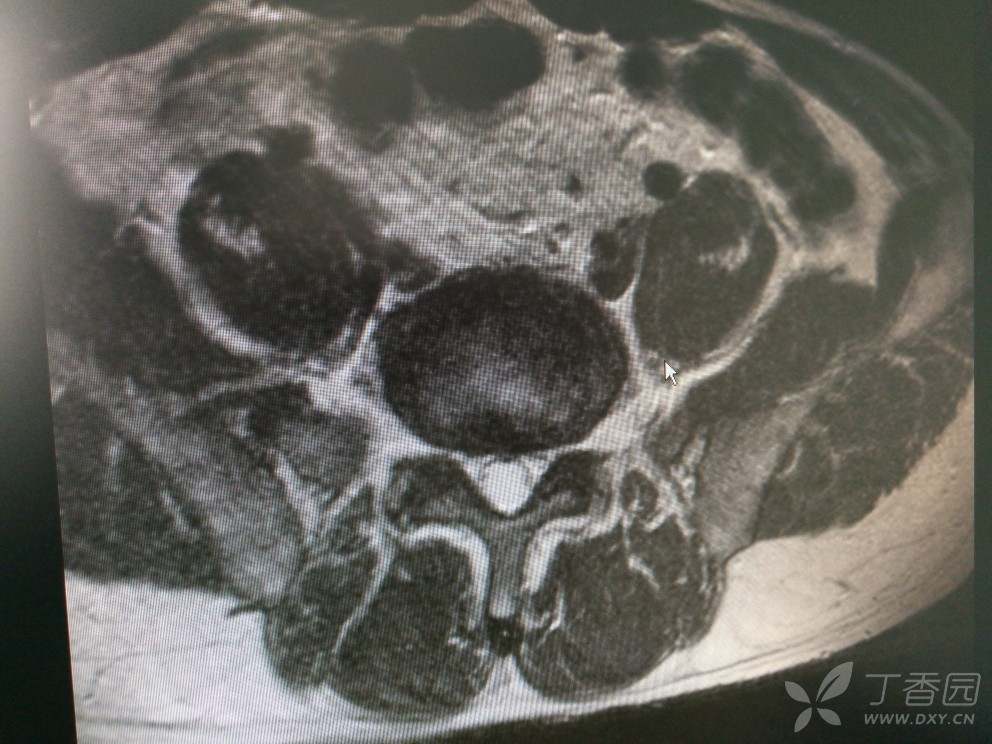

入院查MRI

我想问还是考虑L4/5 L5/S1椎间盘的变性引起的吗?